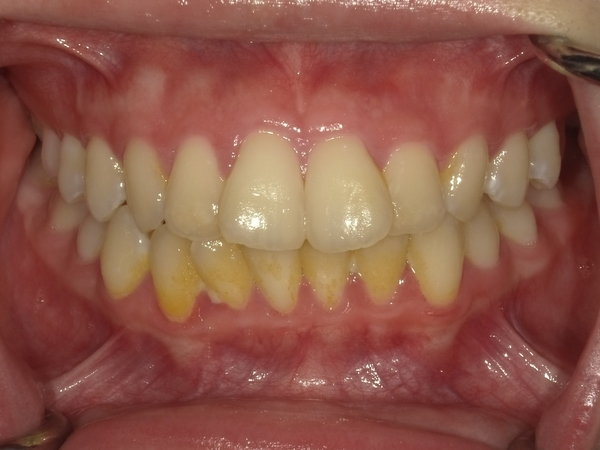

ガタガタとした歯並びや八重歯(叢生)CASE72